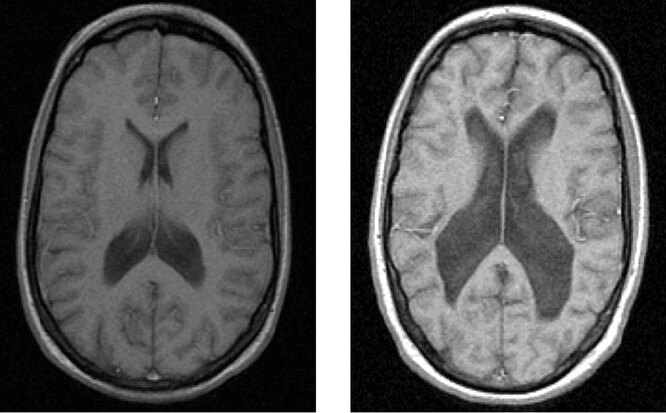

>>943049

Это пиздёж, это не шизофрения а какая-нибудь деменция. От шизофрении не образуются полости в мозге.